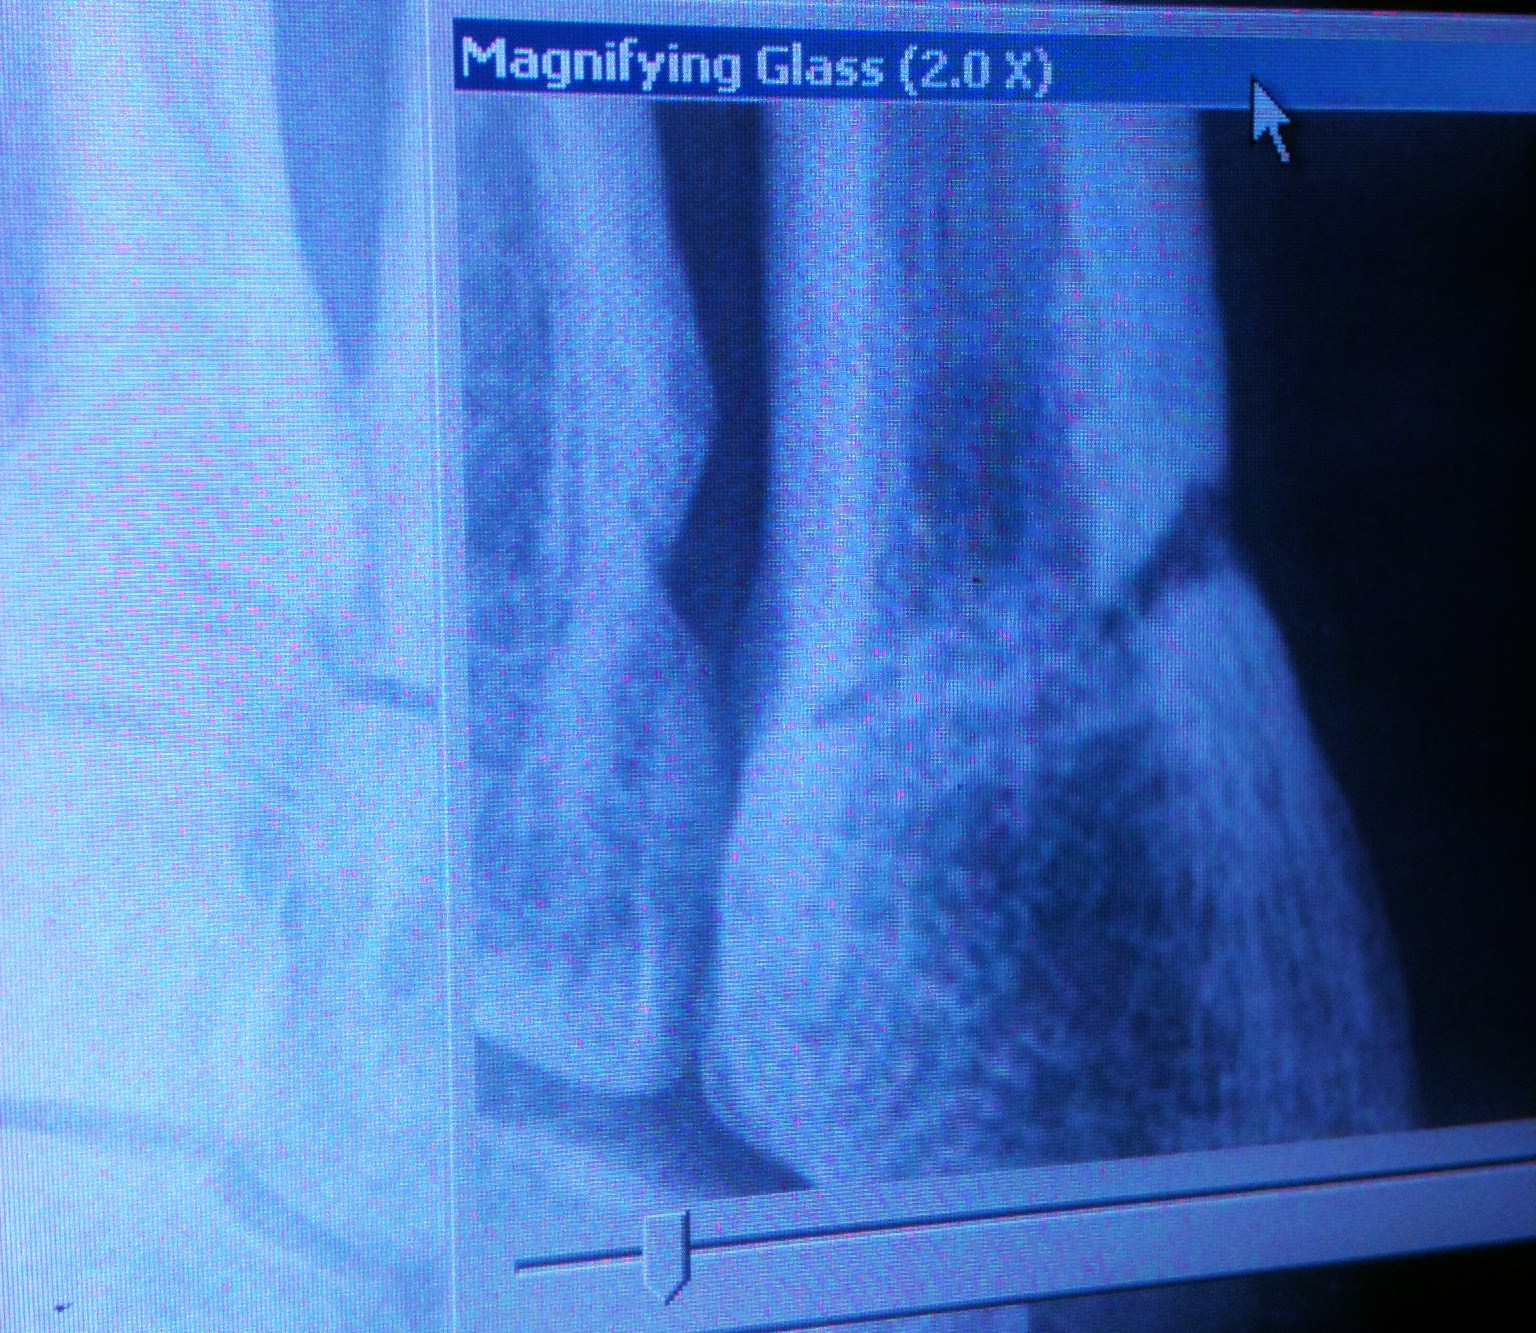

Back to the point. Last summer after snapping my 5th metatarsal for the second time in mere months I had a follow up xray six weeks out that could not have been any worse. Here's the evidence of just how bad that was. A month and a half after breaking my foot and it had actually gotten worse, not better.

Late June 11 - 6 weeks out